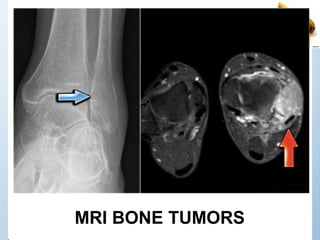

MRI BONE TUMORS